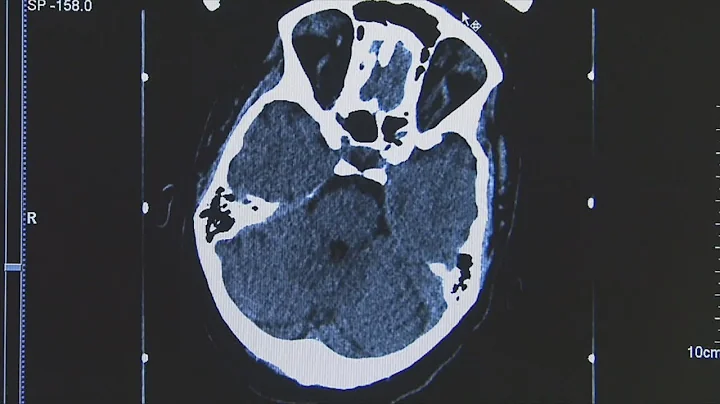

First Trial Of Dbs For Stroke Rehabilitation: Insights On The Underlying Science

A scientist involved in Cleveland Clinic's newly launched study of neuromodulation for post-stroke recovery speaks to the science ...